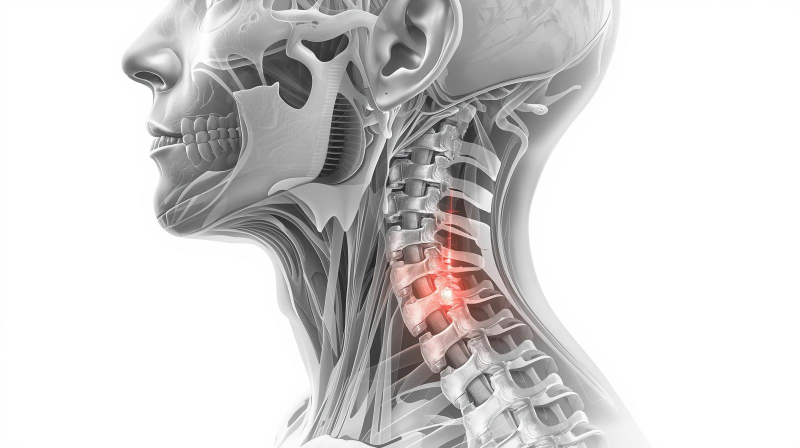

2. 목뼈와 그 변형의 이해

(1) 정상 목뼈

- 측면에서 보았을 때 C자 곡선이 자연스러운 상태

- 충격 흡수 및 균형 유지

(2) 일자목 (Straight Neck)

- C자 곡선이 사라지고 일자로 펴진 상태

- 원인: 잘못된 자세, 장시간 독서·스마트폰 사용

- 증상: 만성적인 목·어깨 통증, 피로, 긴장성 두통

(3) 거북목 (Forward Head Posture)

- 목뼈의 커브 소실 + 머리가 앞으로 빠진 상태

- 어깨가 굽고 등이 구부정해 보임

- 목 각도가 앞으로 기울어질수록, 목 뒤 근육이 지탱해야 할 무게가 급격히 증가